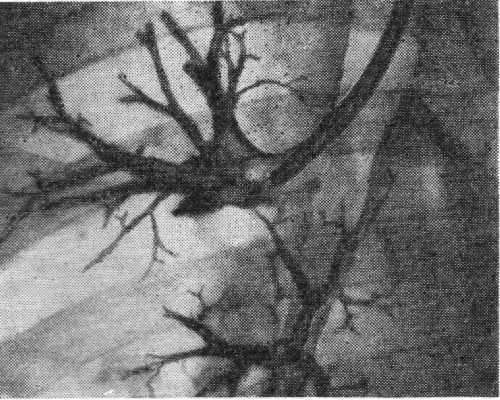

Наибольшее применение получили чрезгортанные способы Б. с введением катетера трансназально или трансорально. Наиболее распространена, проста и доступна методика трансназального введения катетера (рис. 1). При трансоральном чрезгортанном способе катетер вводят через бронхоскоп, интубационную трубку (лучше двухпросветную) или двухпросветную трубку Карленса. Эти методические приемы используют при поднаркозной Б. с управляемым дыханием. Двухпросветная интубационная трубка предотвращает затекание контрастного вещества в противоположное легкое, а двухпросветная трубка Карленса, использование которой возможно и под местной анестезией, позволяет к тому же аспирировать содержимое бронхов до п после контрастирования.

Контрастное вещество может поступать в те или иные отделы бронхиального дерева путем изменения положения тела больного, стекая в определенном направлении в силу своей тяжести (позиционная Б.), или путем раздельного заполнения под давлением предварительно катетеризированных бронхов (прицельная Б.). На практике иногда пользуются комбинацией прицельной и позиционной Б.

Рис. 2. Катетеры и зонды для бронхографии: 1 — управляемый катетер Розенштрауха; 2 — управляемый катетер Розенштрауха — Смулевича; 3—5 — зонды Метра.

Для прицельного заполнения бронхов применяют специальные наборы полуупругих резиновых зондов, кончики которых изогнуты под различными углами, соответствующими углам отхождения отдельных бронхов (зонды Метра). Шагом вперед явилась идея управляемых с помощью нити катетеров (катетеры Розенштрауха, Розенштрауха — Смулевича), к-рым в нужный момент под рентгеноскопическим контролем можно придать необходимый изгиб (рис. 2). При потягивании за выведенную наружу нитку кончик катетера может быть изогнут и путем вращения направлен в тот или иной бронх (рис. 3). В последние годы в практику входят управляемые катетеры, изготовленные из прозрачных пластических масс, содержащих рентгеноконтрастное вещество, сконцентрированное в виде тонкой нити в стенке катетера.